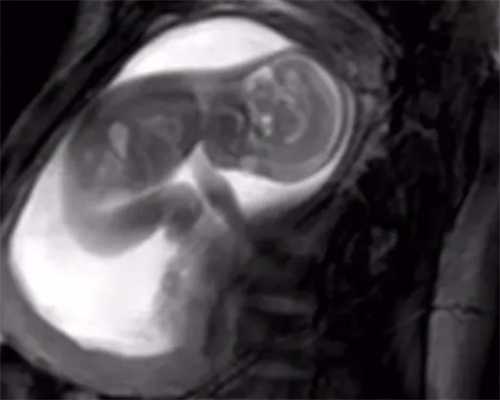

很多夫妇结婚多年,一直没有办法顺利的拥有自己的孩子,也使得不少家庭出现了矛盾,对于这类人群而言,试管婴儿是不错的选择,能够帮助他们通过助孕受精的方式拥有自己的孩子。

试管婴儿的好处是对于一些有女性先天性的输卵管管堵塞患者者是怀孕困难的患者可以通过试管婴儿的方式来帮助怀孕,并且挑选到优质的胚胎,但是试管婴儿的费用一般都是比较高的,一般如果在培养试管婴儿的时候,一次不成功,那么做试管婴儿的时候就会反复的进行胚胎的培育,这样对身心都是会有疲惫的感的。